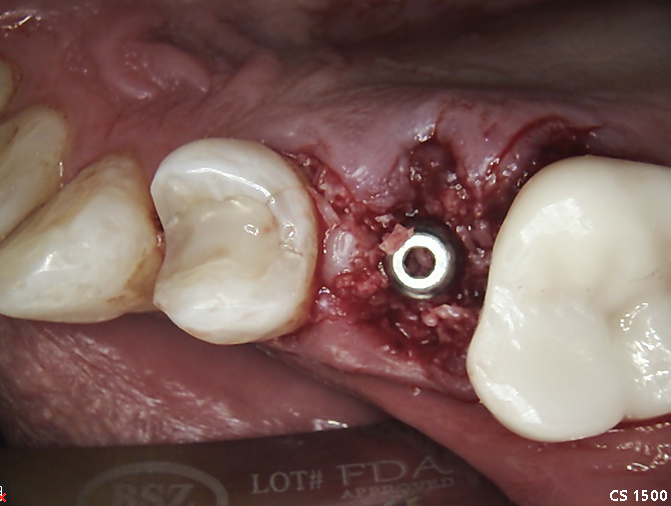

Practical case with DSI Premium Spiral Implant